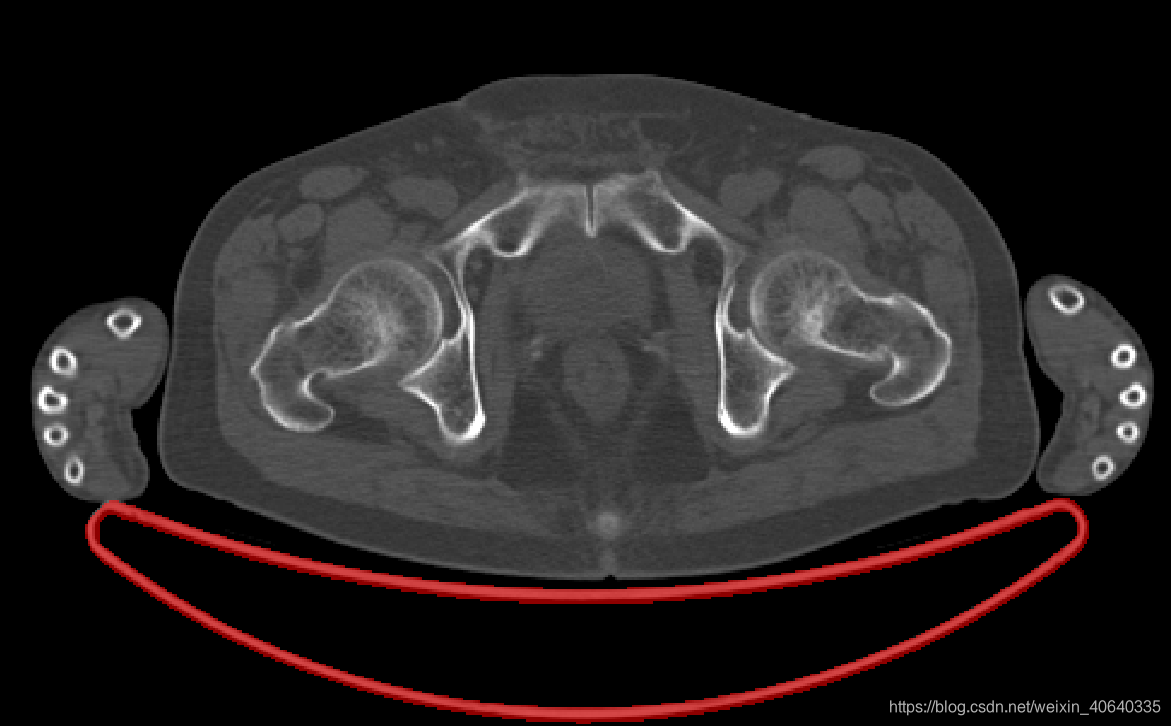

不理想的情况指的是,人体与机床有相连,导致取连通域后得到的mask其实包含有机床部分,这种情况在实际中也经常碰到,因此需要去除机床部分,尝试了以下两种方法:

1.形态学方法:

思路:开操作、腐蚀,希望能断开人体与机床部分相连的地方,然后再取一次最大连通域

缺点:该方法在人和机床相连情况不太严重时有一定效果,但是容易导致获得的人体部分经过形态学处理后有点问题

2.先获取机床的mask:

思路:在有多例CT数据的情况下,每例CT图像取到最大连通域(可能包含机床)后,我们叠加所有连通域,由于人体与机床相连的位置各不相同,而机床的位置是固定的,因此相连的地方的重叠次数不高于机床部分,我们保留重叠次数大于设定阈值的区域,再去掉此时的最大连通域(即人体部分),最后经过一下形态学的简单处理,即可获得机床部分的mask

(注意:需要保证这批数据由同样一台机器扫描得到,不然CT不能简单地进行重叠)

机床MASK示例:

红色部分就是机床mask了,结果还不错,再配合最开始的方法,获得人体的mask